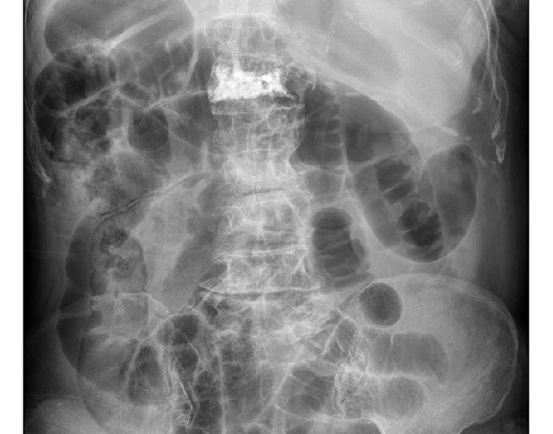

There is no known diagnosis

of gastrointestinal disease, and lab tests and imaging were reported as normal.